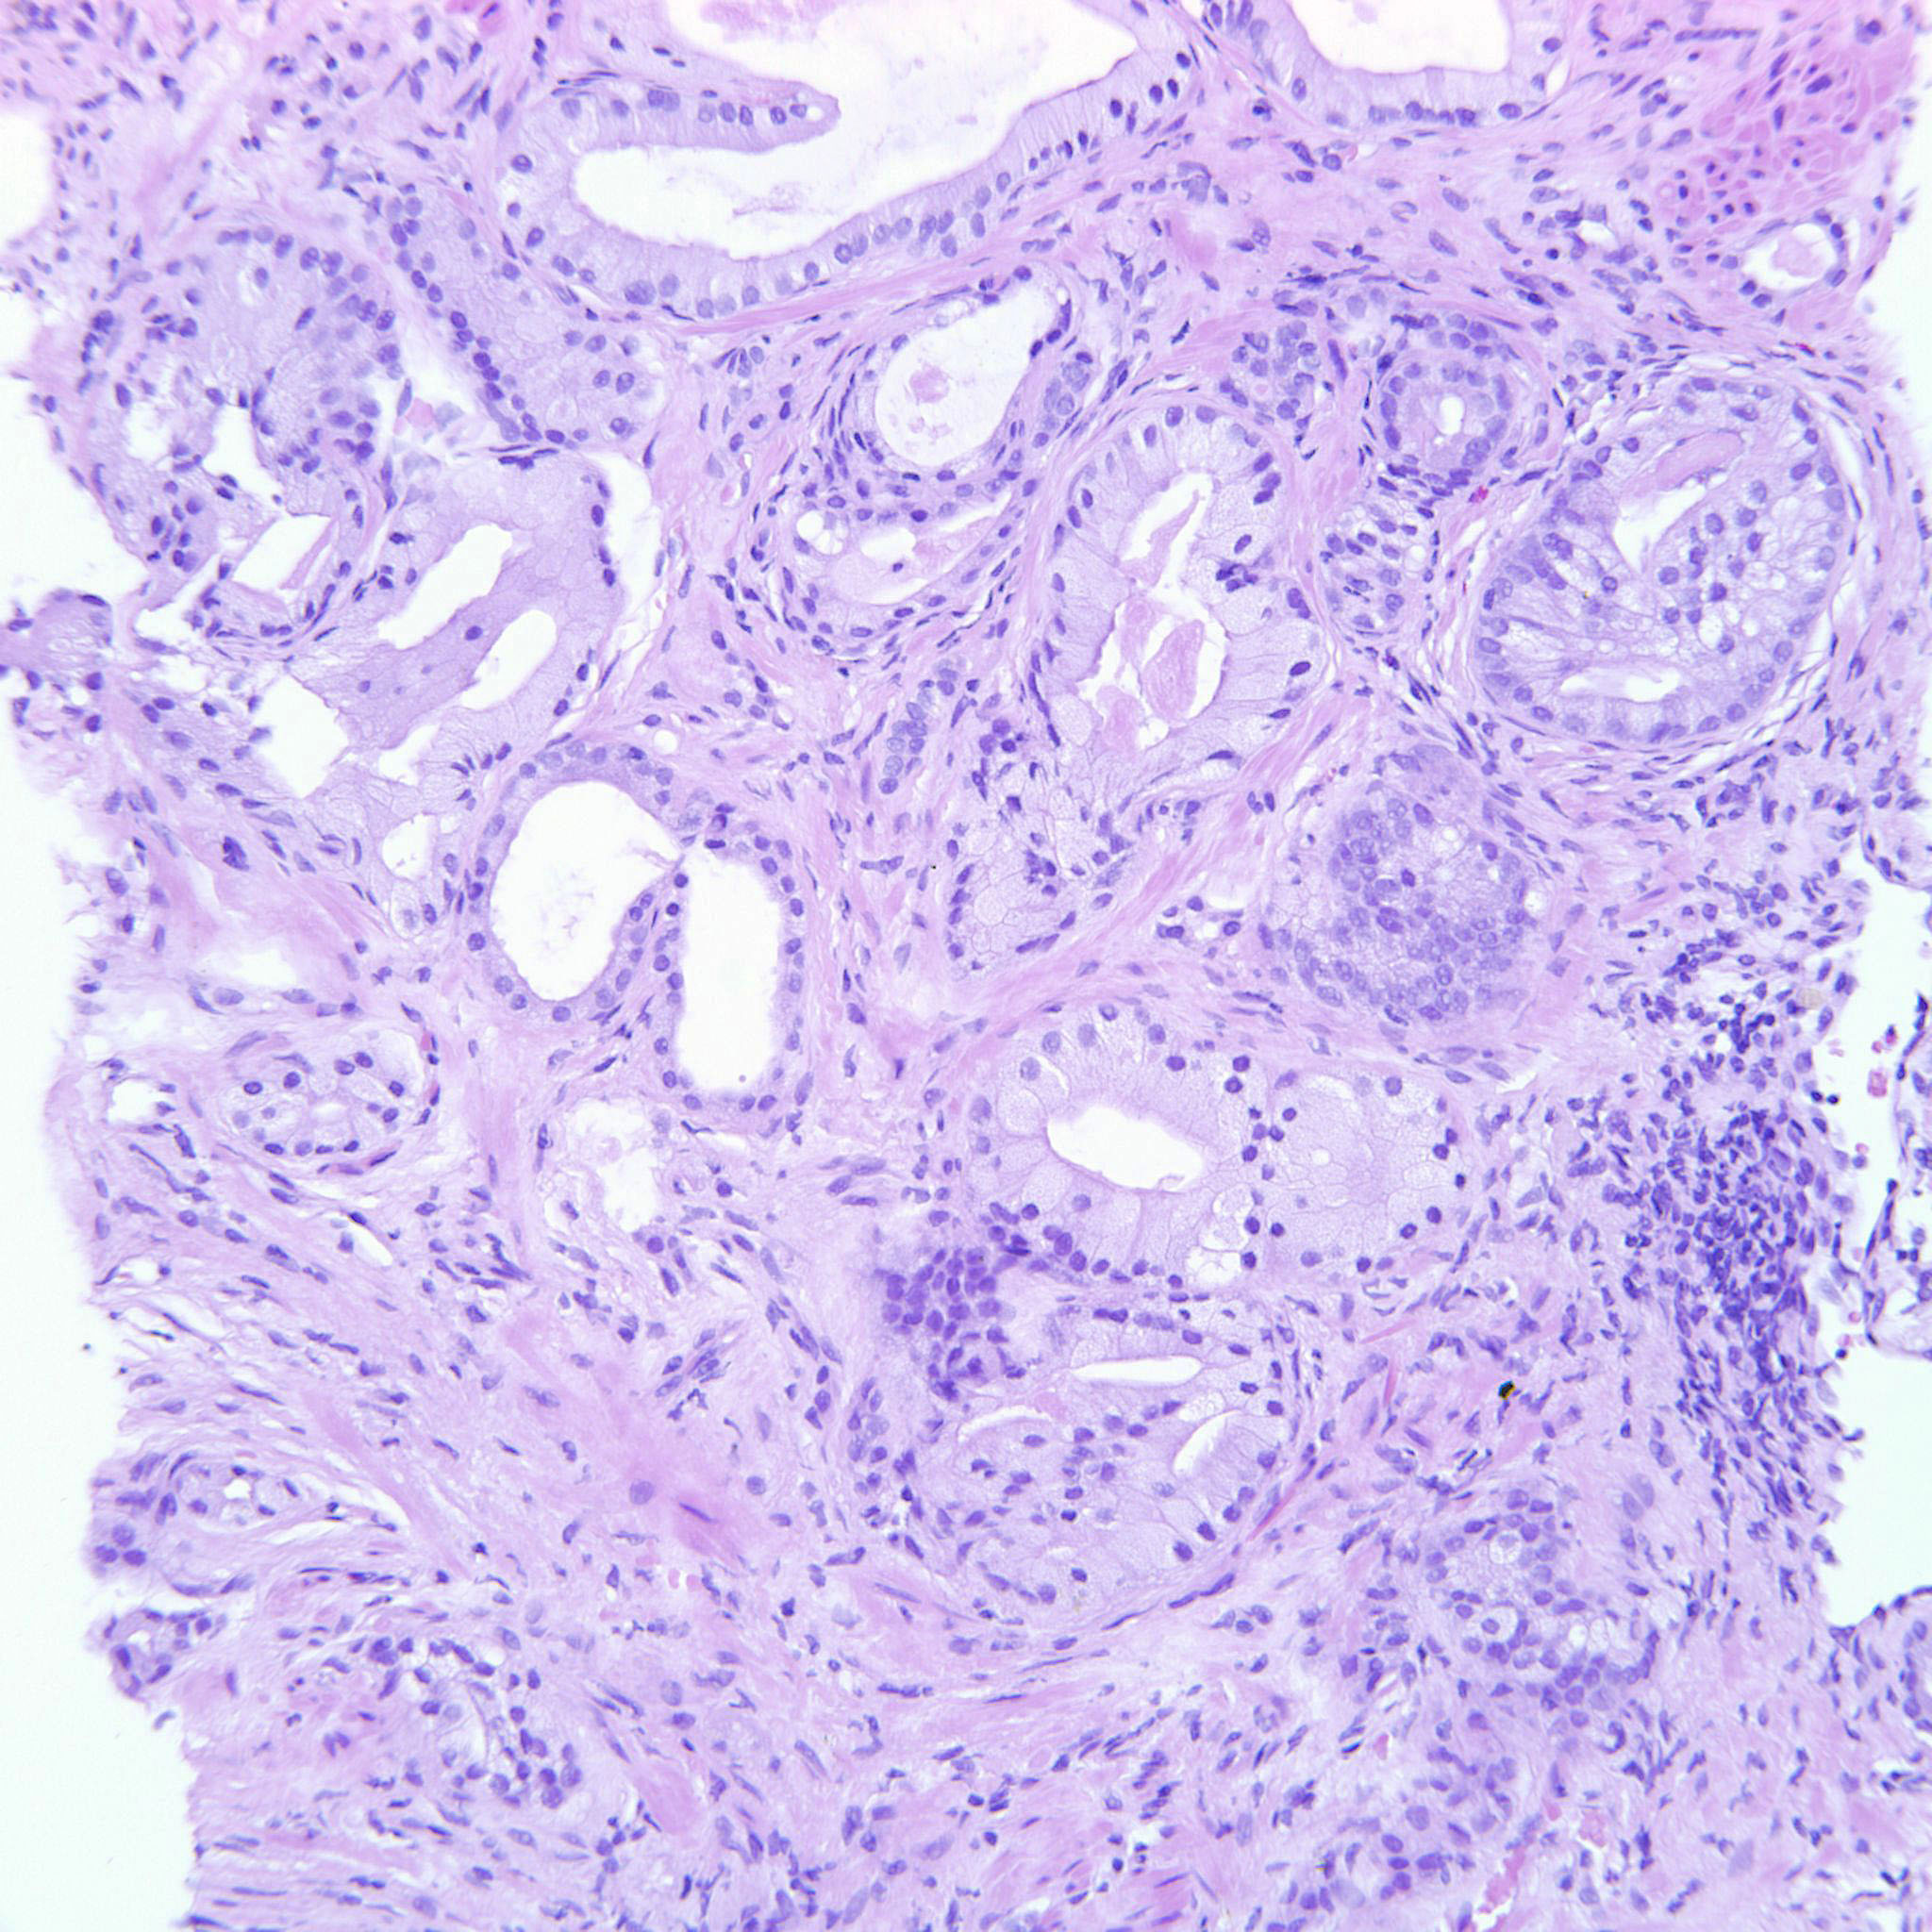

Prostate cancer grading

Case ID: 699